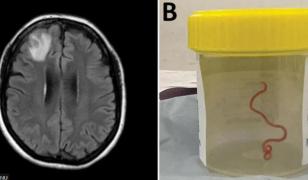

"Brusc, scoate chestia asta care mişcă". Vierme viu, găsit în creierul unei femei. Se plângea de dureri de cap, medicii credeau că are o tumoare

"Brusc, scoate chestia asta care mişcă". Vierme viu, găsit în creierul unei femei. Se plângea de dureri de cap, medicii credeau că are o tumoareCaz şocant pentru neurochirurgii din Australia. Aceştia au scos un parazit de aproape 10 centimetri lungime din creierul unei...

Un vierme viu a fost descoperit, în premieră, în creierul unei australience. De regulă, parazitează doar şerpi şi canguri

Un vierme viu a fost descoperit, în premieră, în creierul unei australience. De regulă, parazitează doar şerpi şi canguriUn vierme cilindric, care parazitează de obicei corpul şerpilor, a fost descoperit pentru prima dată la o fiinţă umană, fiind...